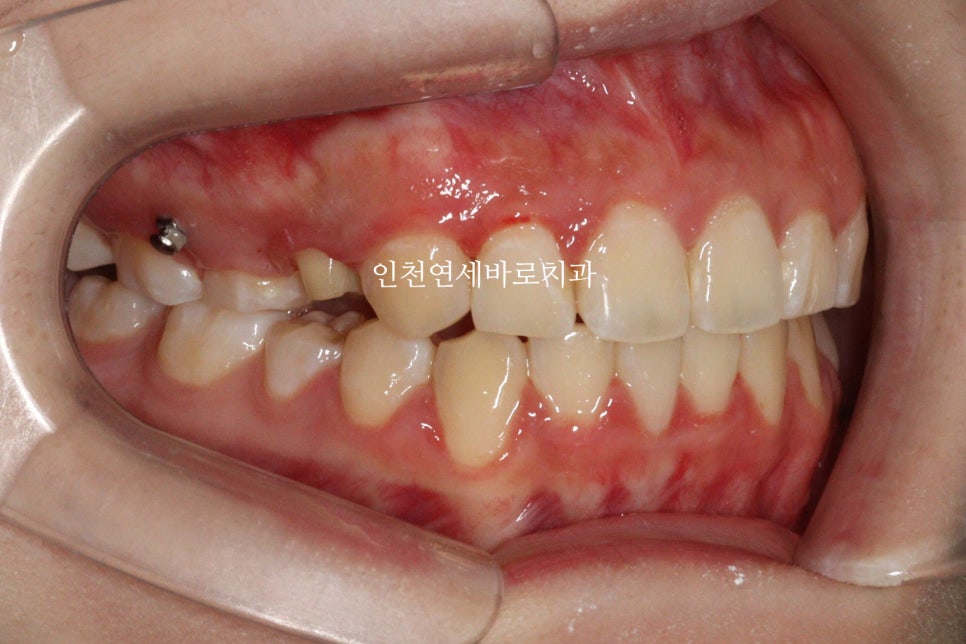

화살표 치아가 임플란트 였습니다.

첫번째 세트가 끝났을때의 모습입니다.

교합이 맞지 않고 아쉬운 부분이 많이 보였습니다.